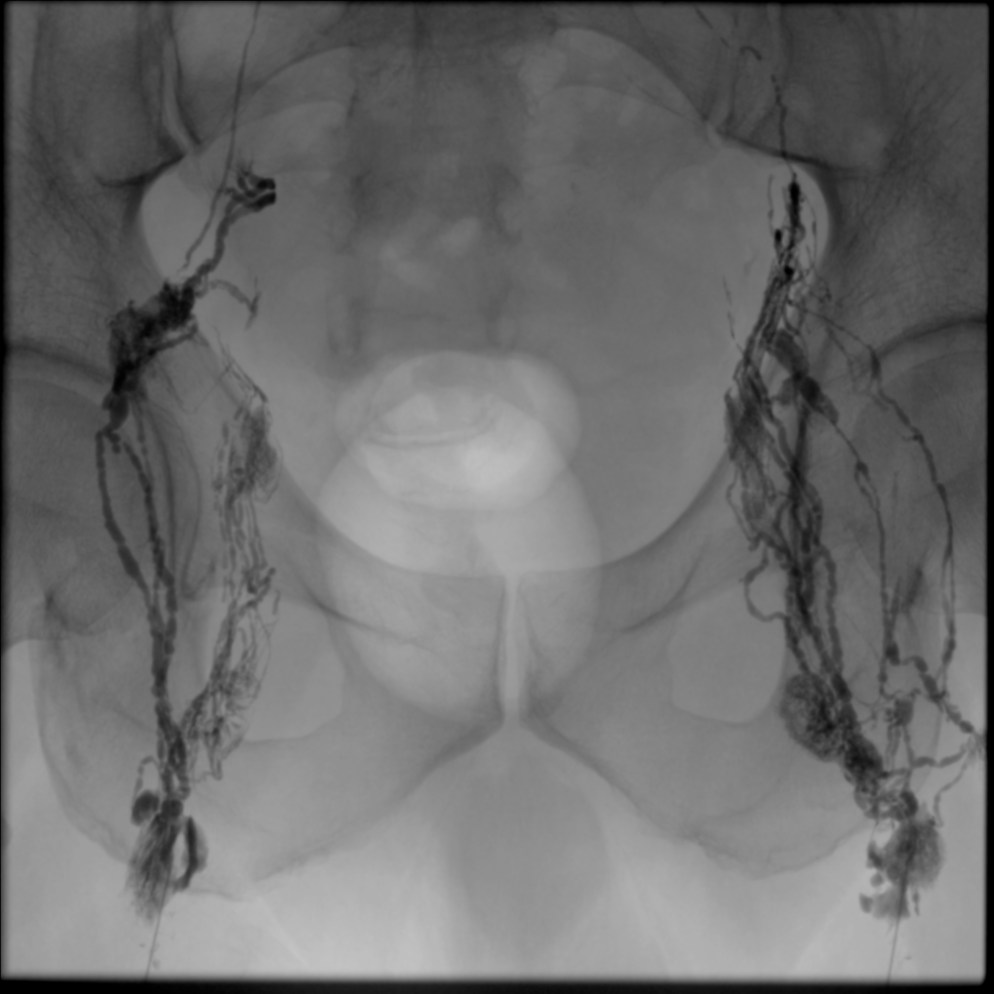

In this technique, an inguinal lymph node is directly accessed under ultrasound guidance with a 25-gauge spinal needle with the needle tip positioned in the hilum of the node (Figure 1). Subsequently, an oil-based contrast agent (Lipiodol, Guerbet Group, Princeton, NJ) is injected at a rate of about 1-2 mL per 5 minutes (Figure 2). If successful, immediate opacification of the lymphatic vessels is observed under fluoroscopy (Figure 3).